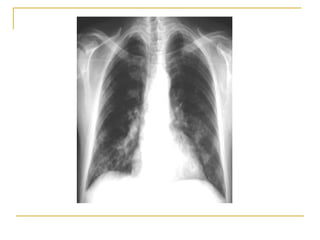

Neumonía por  Pneumocystitis carinii.  Patrón pulmonar intersticial bilateral.